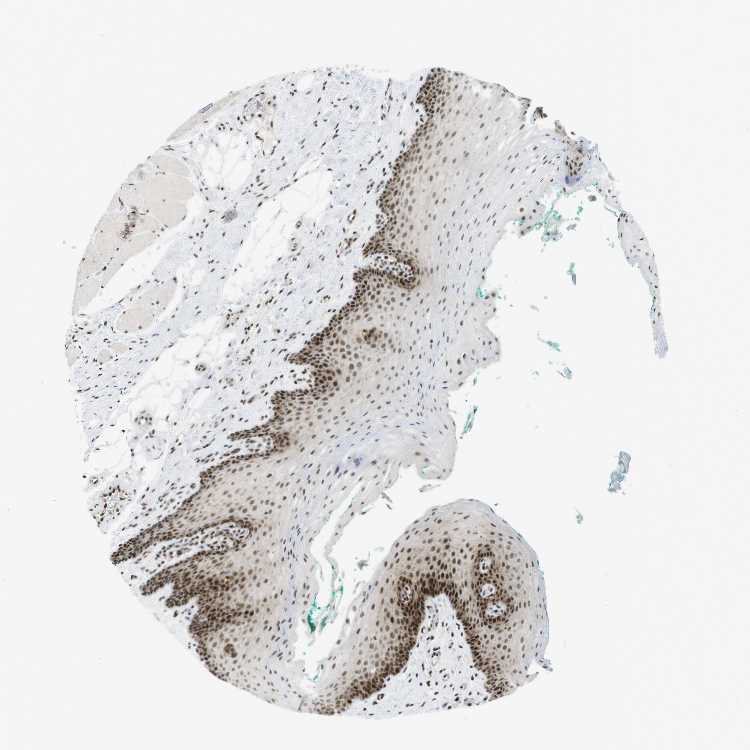

TISSUE PRIMARY DATA ORAL MUCOSA Show tissue menu

ORAL MUCOSA - Antibody stainingi

Antibody staining in the annotated cell types in the current human tissue is reported as not detected, low, medium, or high, based on conventional immunohistochemistry profiling in selected tissues. This score is based on the combination of the staining intensity and fraction of stained cells.

Each image is clickable and will lead to virtual microscopy that enables deeper exploration of all samples and also displays staining intensity scores, fraction scores and subcellular localization as well as patient and tissue information for each sample.

Antibody HPA028129Antibody CAB016315

Squamous epithelial cells HighHigh